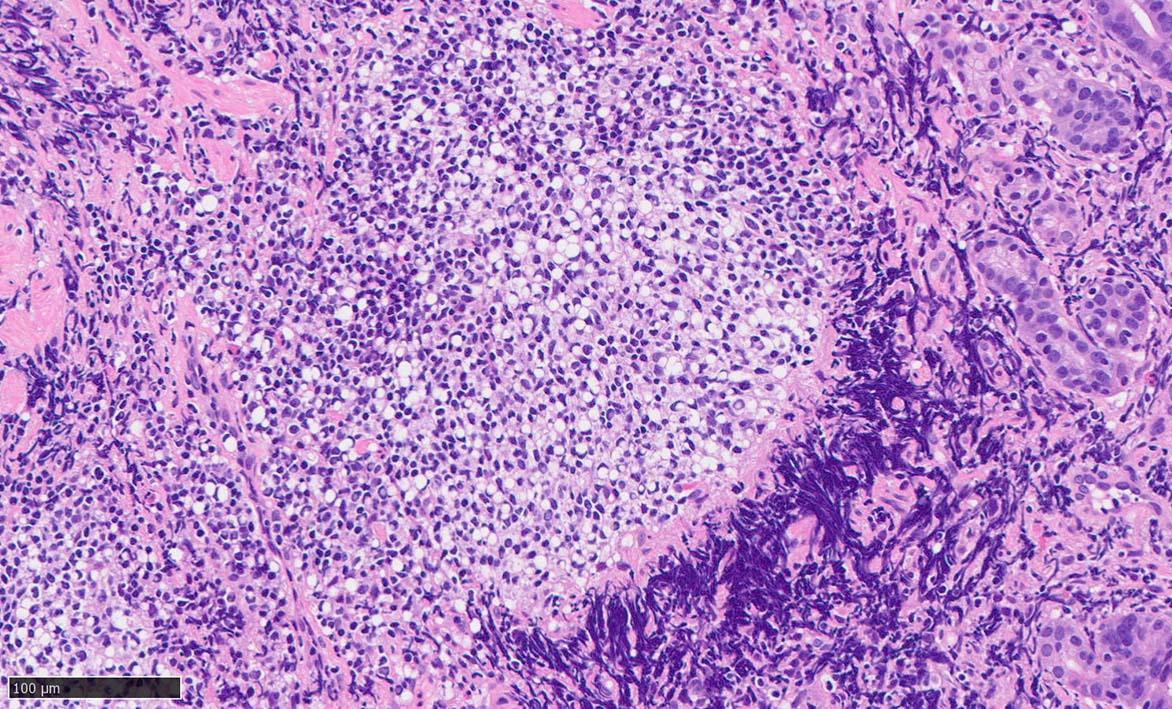

60 year-old male. 胃生検組織

stomach biopsy, HE

x200